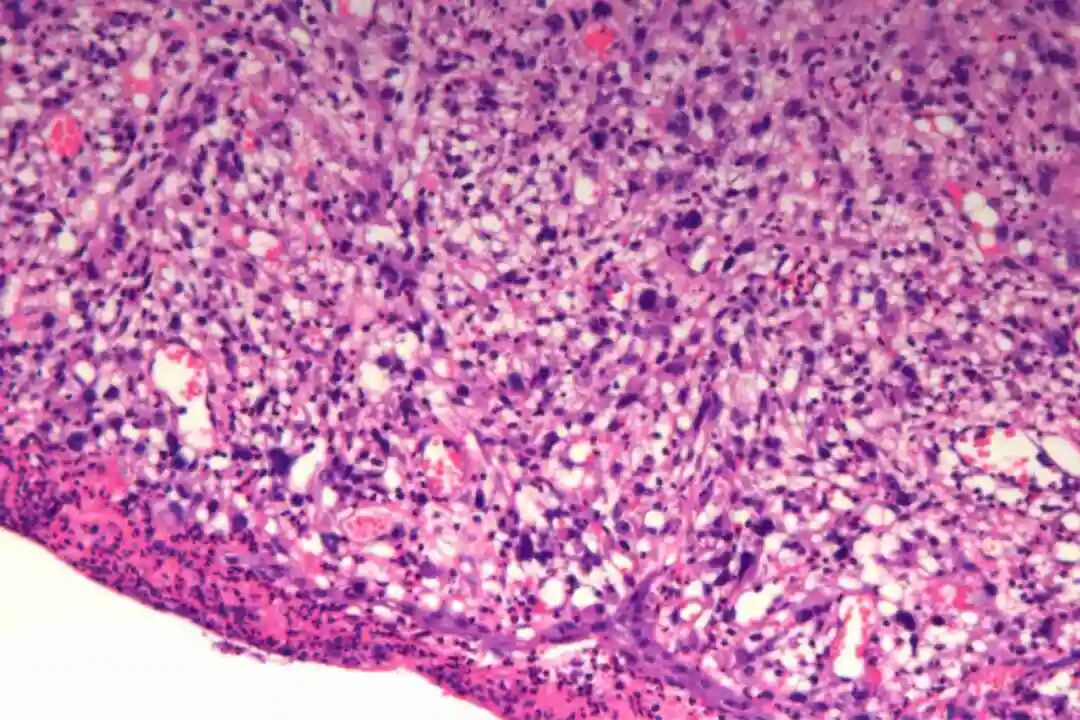

镜下表现

低倍镜:梭形细胞呈交织束状排列,浸润真皮深层或皮下脂肪

高倍镜:细胞核两端钝圆("雪茄形"),核异型性程度因分级而异;核分裂象(关键指标):低级别<5/10HPF,高级别≥5/10HPF;特征性胞质嗜酸性(肌源性分化)。

1、大体形态:界限不清的灰白色质硬肿块,切面呈旋涡状或鱼肉样;坏死/出血可见于高级别肿瘤。

2、镜下特征

低倍镜:梭形细胞呈交织束状排列,浸润真皮深层或皮下脂肪。

高倍镜:细胞核两端钝圆("雪茄形"),核异型性程度因分级而异;

核分裂象(关键指标):低级别<5/10HPF,高级别≥5/10HPF;特征性胞质嗜酸性(肌源性分化)。